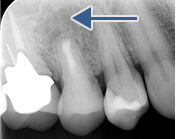

被せ物をした歯の違和感により来院されました

レントゲン写真により経過を確認します

黒い影は骨が溶け膿を持っている

黒い影が無くなり骨の再生が認められ経過は良好です